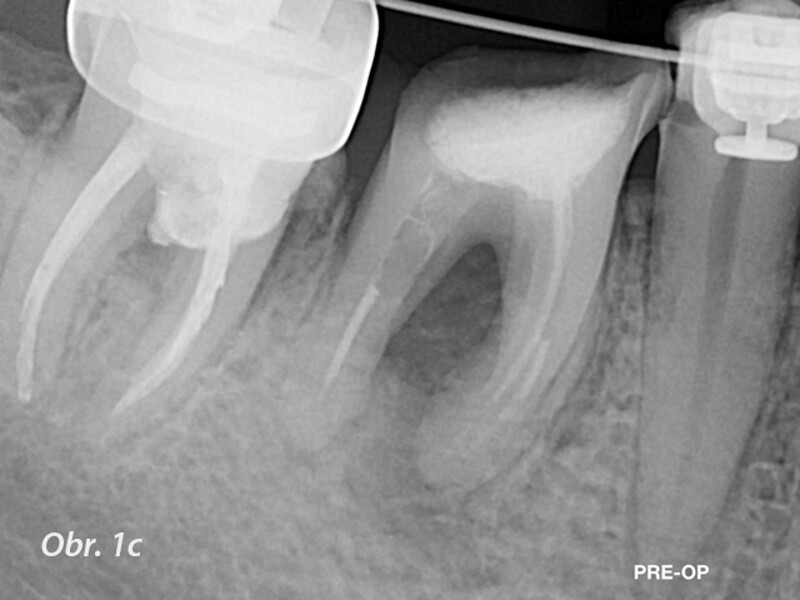

Řešení endodontických selhání